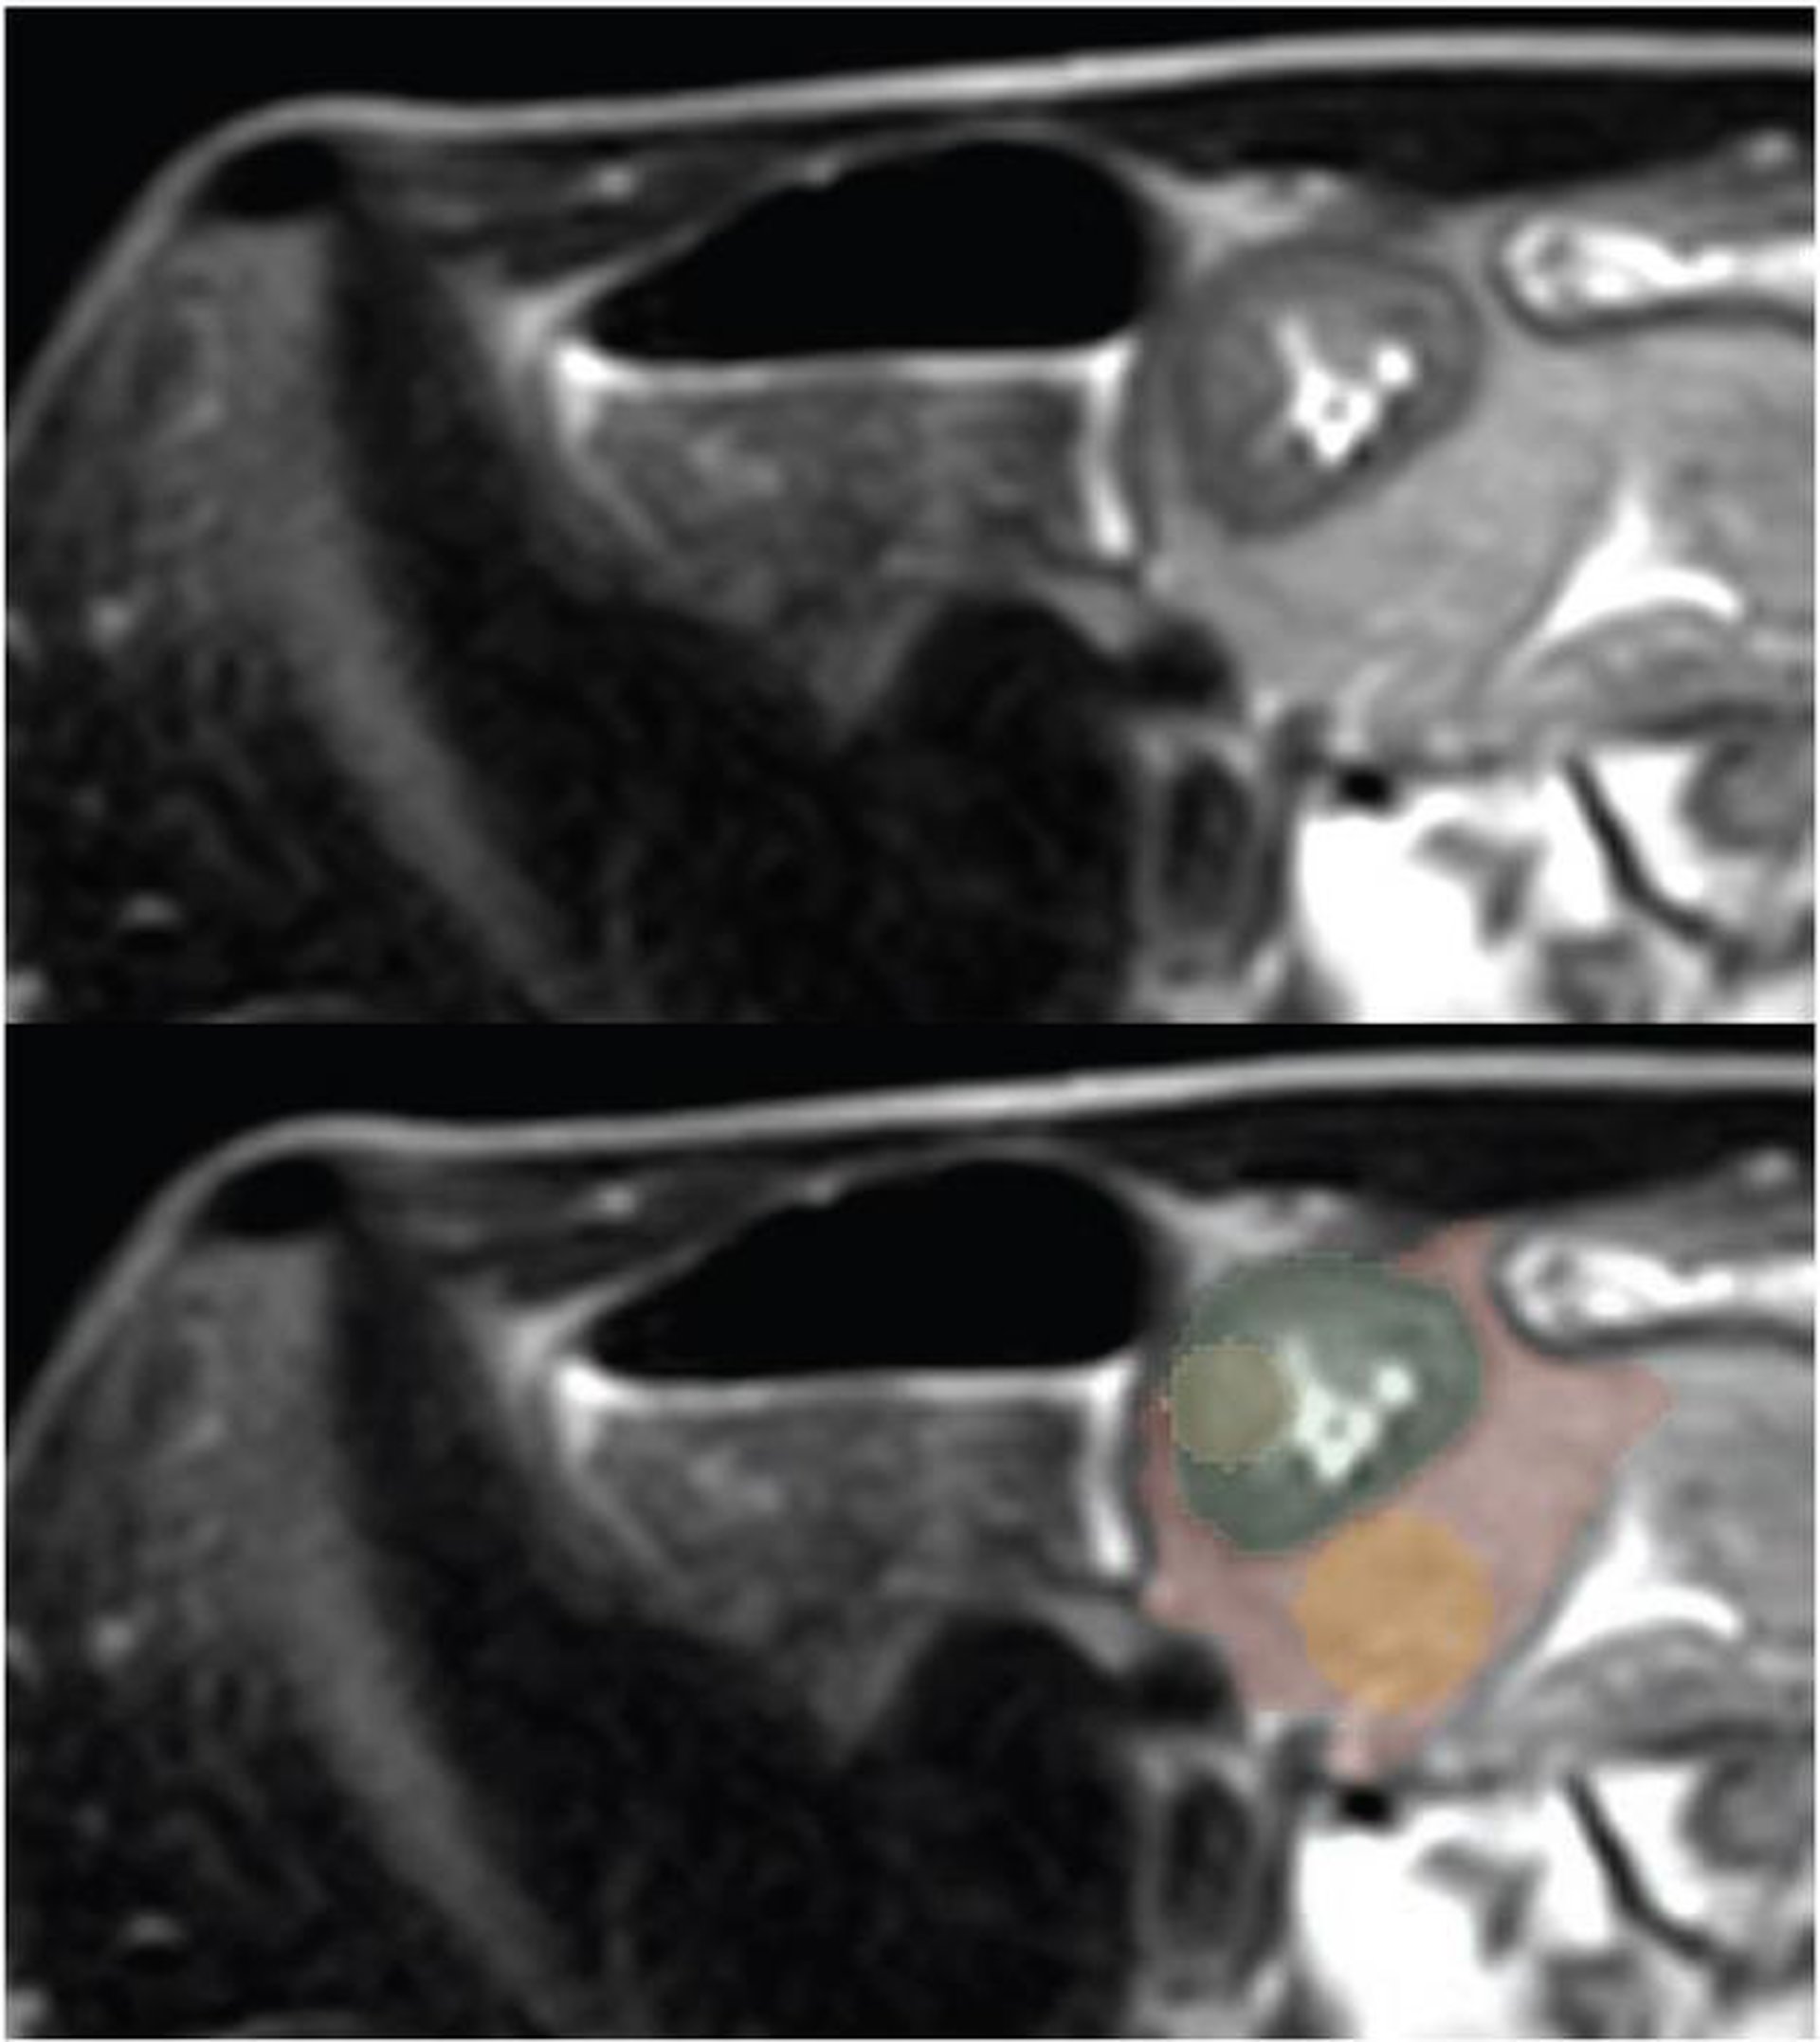

Las imágenes SSFSE axiales ponderadas en T2 muestran el mayor grosor terminal.

El manuscrito identificó a los pacientes que se sometieron a enterografía por resonancia magnética (ERM) por sospecha de enfermedad de Crohn ileal: participantes con EC ileal recién diagnosticada o que sirvieron como controles sanos desde diciembre de 2018 hasta octubre de 2021. Usando imágenes SSFSE axiales ponderadas en T2, un radiólogo seleccionó dos rebanadas que mostraban el mayor engrosamiento de la pared ileal terminal.

A continuación, se segmentaron cuatro ROI, se extrajeron características radiómicas de cada una y se entrenaron modelos de máquina de vectores de soporte para catalogar la presencia de EC ileal. Tres radiólogos abdominales pediátricos especializados clasificaron de forma independiente la presencia de EC ileal en imágenes SSFSE, con diagnóstico clínico tras endoscopia positiva y biopsia como estándar de referencia.

En última instancia, el modelo radiómico de mejor rendimiento en este manuscrito aceptado por la AJR utilizó un ROI de pared intestinal redonda en la zona de mayor engrosamiento del íleon terminal, con un AUC de 0,95 y una precisión del 89,6 por ciento. Ensamblando este modelo radiómico con un modelo clínico se obtuvo un AUC de 0,98 y una precisión del 93,5 por ciento. Por su parte, los tres radiólogos especializados alcanzaron precisiones del 83,7%, 86,7% y 88,1%.